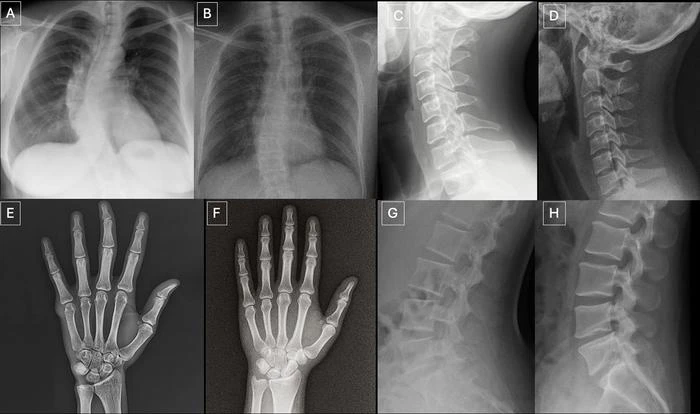

The study identified common features of synthetic X-rays.

"Deepfake medical images often look too perfect,” Dr. Tordjman said. “Bones are overly smooth, spines unnaturally straight, lungs overly symmetrical, blood vessel patterns excessively uniform, and fractures appear unusually clean and consistent, often limited to one side of the bone."

Seventeen radiologists from 12 different centers in six countries (United States, France, Germany, Turkey, United Kingdom and United Arab Emirates) participated in the retrospective study. Their professional experience ranged from 0 to 40 years. Half of the 264 X-ray images in the study were authentic, and the other half were generated by AI. Radiologists were evaluated on two distinct image sets, with no overlapping between the datasets. The first dataset included real and ChatGPT-generated images of multiple anatomical regions. The second dataset included chest X-ray images—half authentic and the other half created by RoentGen, an open-source generative AI diffusion model developed by Stanford Medicine researchers.